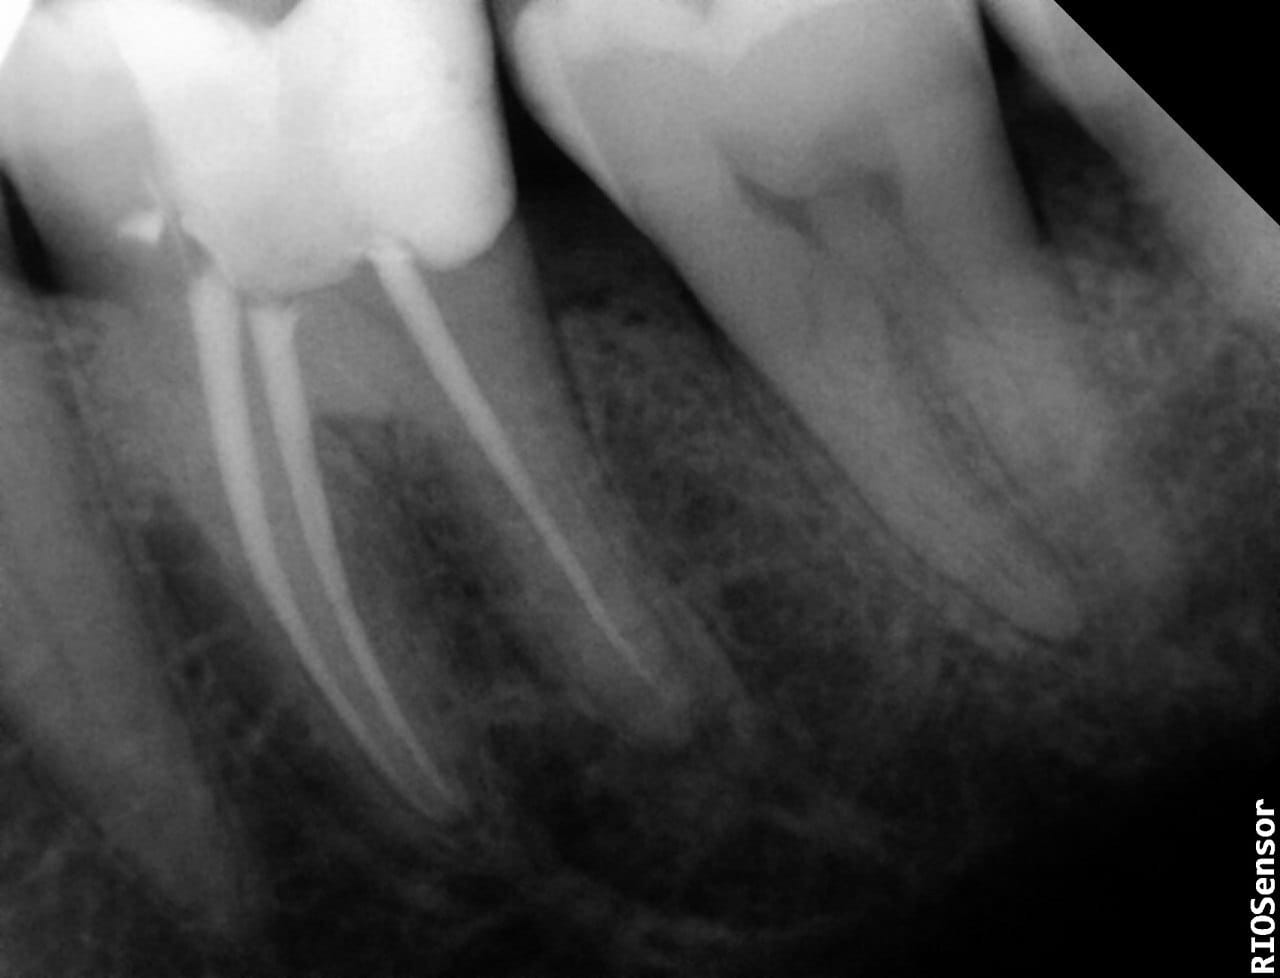

Nerve filling is a procedure by which the damaged nerve tissue in the tooth is removed, and then the space resulting from the removal of these tissues is filled with special filling materials. To preserve the tooth and prevent the spread of infection to the surrounding tissues.

• A small incision is made in the surface of the tooth to reach the root, and then the pulp and nerve of the affected tooth are removed, through the use of special tools.

• Root canal cleaning to eliminate bacteria and sediment.

• Finally, the root canal is filled with a special filler material that prevents the spread of bacteria and infection.